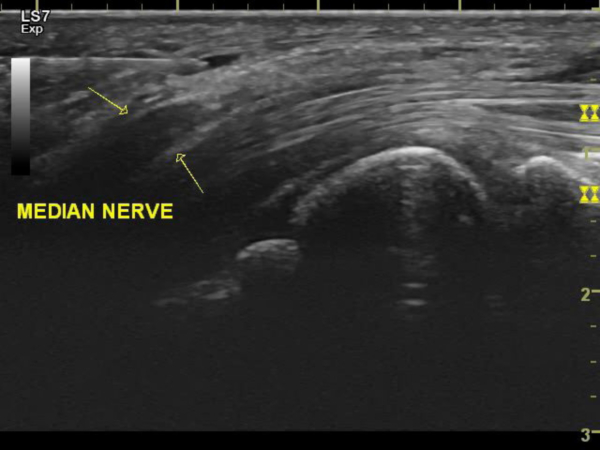

Figure 2. Needling toward median nerve through transverse carpal ligament

저 역시 수근관 증후군을 치료할 때, 도침으로 인대를 절개하고 정중신경(median nerve)을 직접 자극하여 찌릿한 감각을 유발함으로써 포착(entrapment) 부위의 절개 여부를 확인합니다. 마찬가지로 족근관 증후군(tarsal tunnel syndrome)을 치료할 때 역시 경골신경(tibial nerver)에 자극 증상이 나타날 때까지 도침을 자입(刺入)하는 편입니다.

두 질환을 치료할 때에 있어서 자입 깊이와 신경 손상의 상관관계를 밝히는 논문을 쓰기 위해 수근관(carpal tunnel)의 경우 총 11명을 대상으로 신경자극 후(3번째 손가락 끝까지 찌릿한 느낌) 발침(拔鍼)하여 자입 깊이를 확인하였고, 족근관(tarsal tunnel)의 경우 총 10명을 대상으로 신경자극 후(발바닥으로 퍼지는 찌릿한 느낌) 자입 깊이를 확인하였습니다. 그 결과 신경손상이 발견된 경우는 단 한명도 없었습니다.